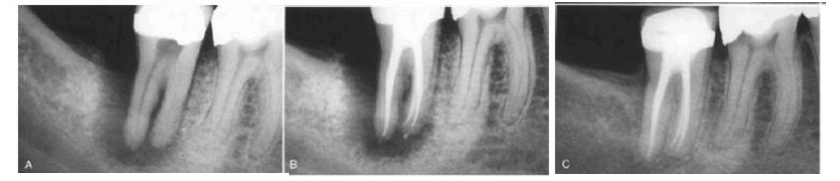

A. This radiolucent lesion has the radiographic appearance of a periodontal lesion. The initial radiograph indicates bone loss from the crest of the ridge around the apices of the tooth. Periodontal probing demonstrates that the gingival sulcus is intact.

B. Root canal treatment completed.

C. Four-year recall shows resolution of the radiolucency.